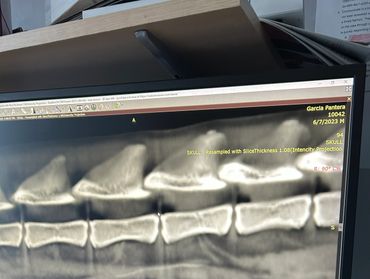

At Harborside Animal Hospital in Clearwater, FL, we are proud to offer CT imaging for pets with fluoroscopy capability. This advanced imaging modality allows us to provide affordable veterinary imaging solutions to the surrounding areas. Our services include evaluations for conditions such as elbow dysplasia, abdominal masses, aural polyps, chronic ear infections, sub lumbar lymph node metastasis checks, contrast-assisted mass spread mapping, complicated oral disease, nasal masses, thoracic metastasis checks, portosystemic shunts, angular limb deformities, collapsing trachea, and urinary contrast studies. Thank you for entrusting us with your patients.